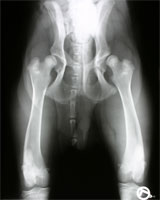

In den Fällen einer extremen Lockerheit der Hüftgelenke kann die Verbesserung der Abdeckung durch den dorsalen Rand des Acetabulums zunächst enttäuschend erscheinen (Abb 14 a, 14 b und 14 c) und ein gewisser Grad an Subluxation noch erkennbar sein. Diese Befunde verschwinden jedoch innerhalb weniger Wochen unter Belastung des Gelenkes, ohne besondere Maßnahmen zu erfordern.

HD vollständige Luxation

Abbildung 14 a: Extreme Lockerheit und Luxation der Articulatio coxae

schwere HD mit Luxation nach DBO

Abbildung 14 b: Bei gestreckten Hüftgelenken erscheint die Hüfte gut stabilisiert.

Abbildung 14 c: In der Beugestellung zeigt sich eine enttäuschende Lockerheit